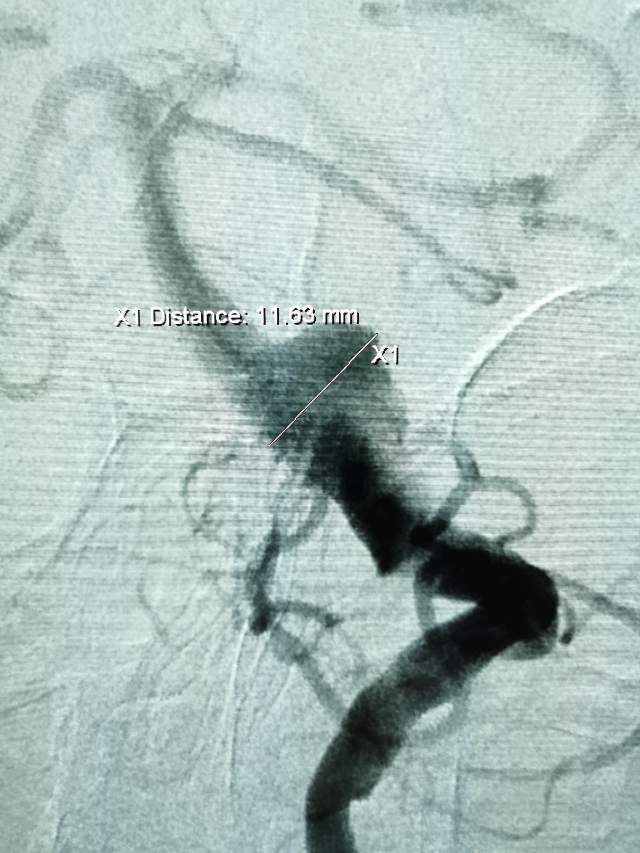

患者男性,34岁,年前自新疆坐车48小时来到我院,诊断:椎基底动脉冗长扩张症,出现脑干压迫症状、后组颅神经症状、部分中组颅神经症状、小脑症状、颅内压增高(220mmHg),症状进行性加重,最大径15mm,血管外面存在血栓造影只能窥见部分,短短两周,病变形态出现明显变化,局部出现明显瘤样凸起(图2-3),手术方案只能临时改变,植入血流导向装置,术后看病人语言、四肢活动均正常,围手术期仍然是一个艰巨的过程,充满了不确定因素,希望患者能安全度过围手术期,早日康复,重返工作岗位~~~